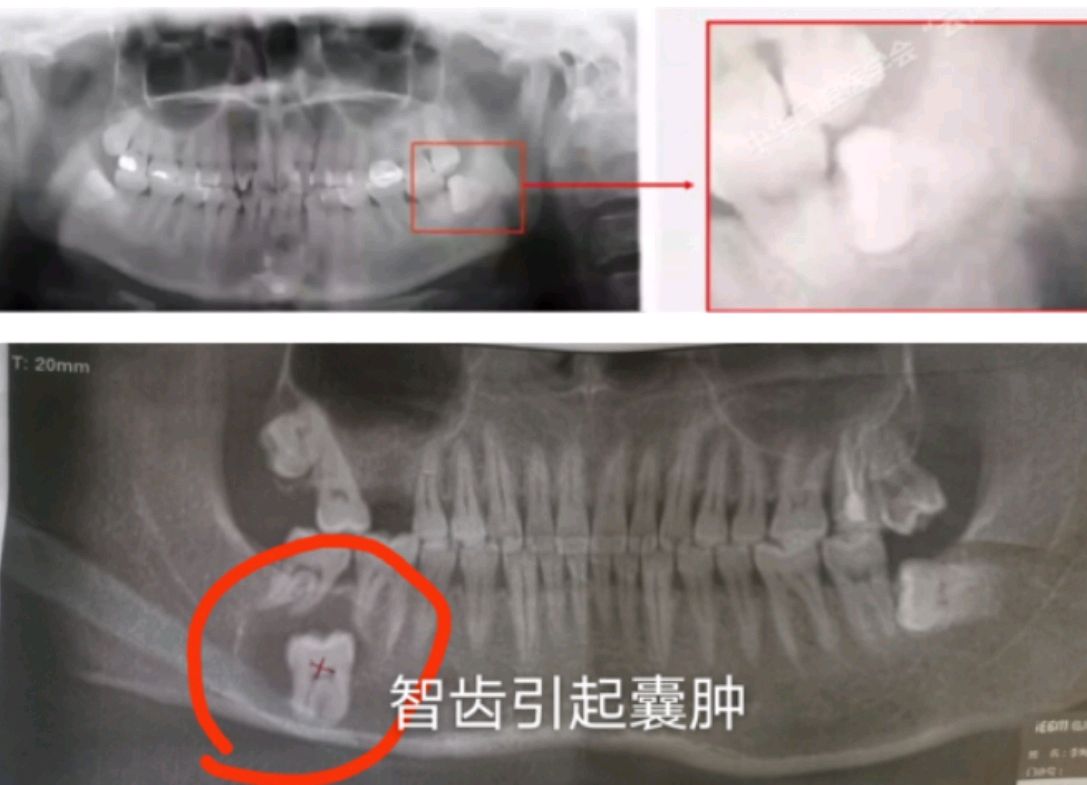

举例的图示智齿都要建议及早拔除